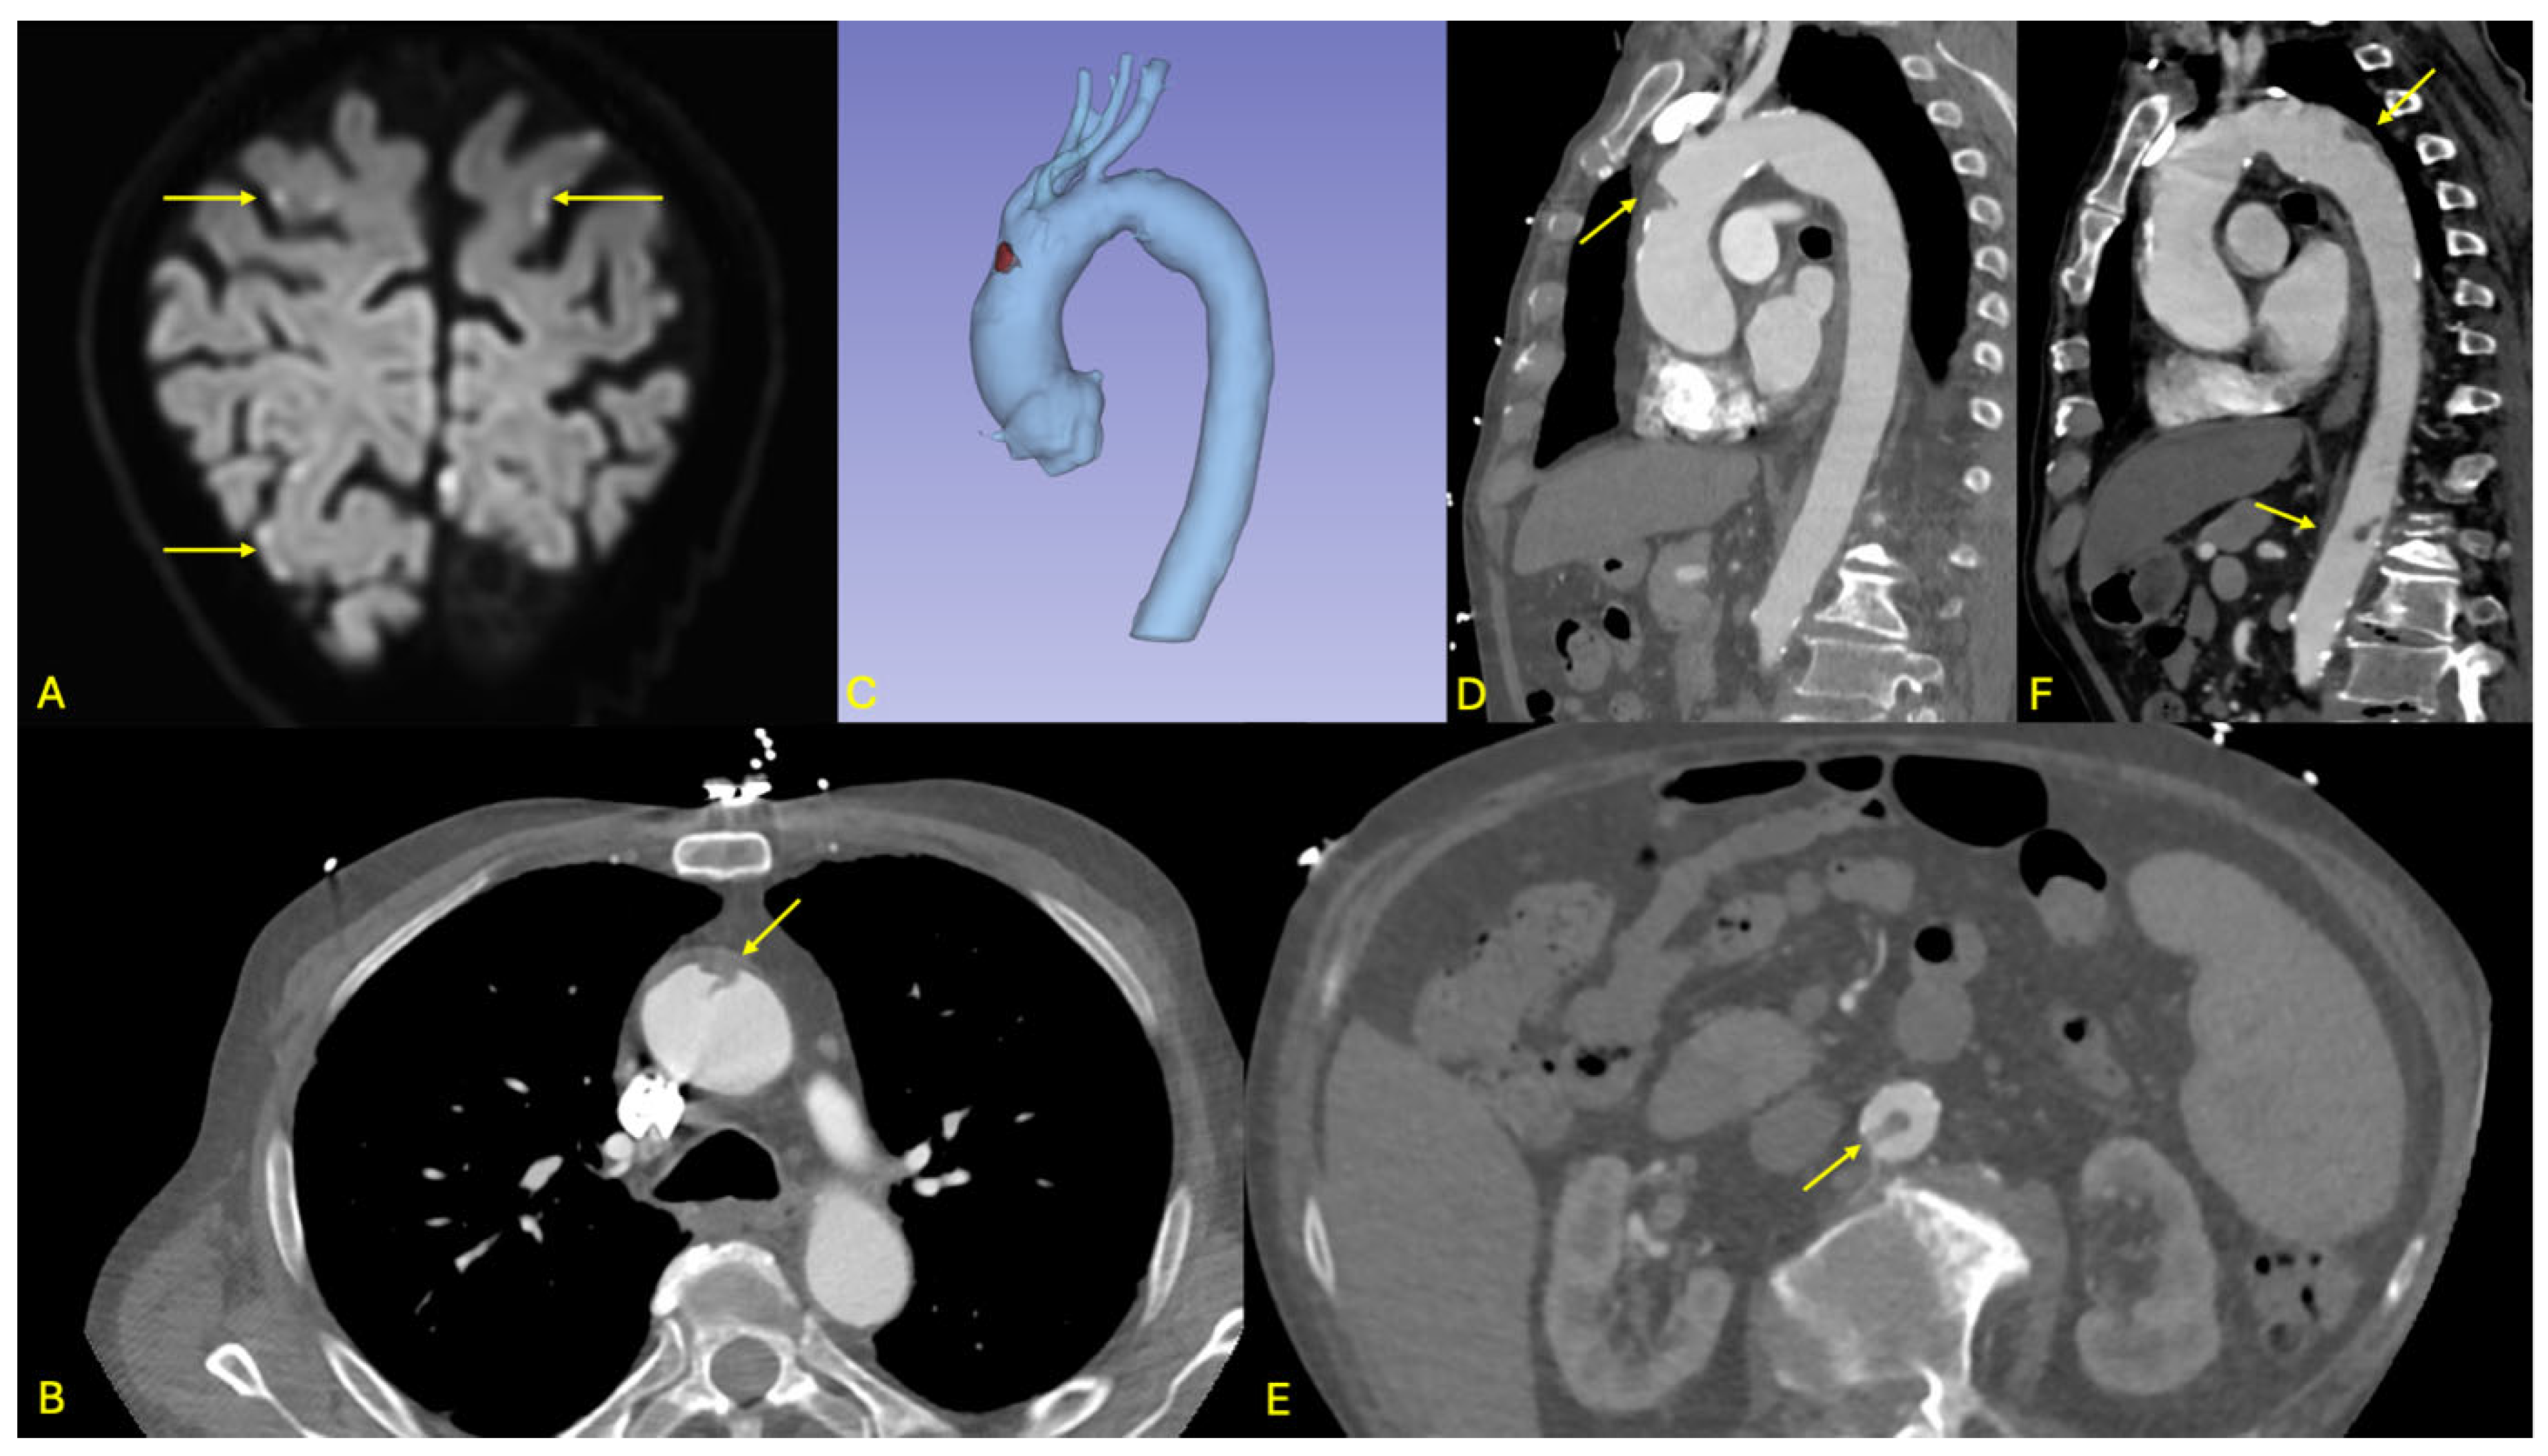

Figure 1. Overview of imaging findings in patient 1. (A,B): Respective axial views from the non-gated and ECG-gated CT angiographies performed at initial imaging work-up showing the impact of ECG-gating on thrombus visualization and contours. (A,B) Lobulated endoluminal structure with no apparent contact with the aorta is visualized on this slice (arrow in B). (C,D): Coronal and sagittal views of the ECG-gated CT angiography showing the cranio-caudal extension of this thrombotic formation. (E): 3D multi-planar reconstruction showing the significance of the thrombus with respect to the aortic lumen, and the attachment to the left aspect of the ascending aorta (arrow). No other thrombi were identified.